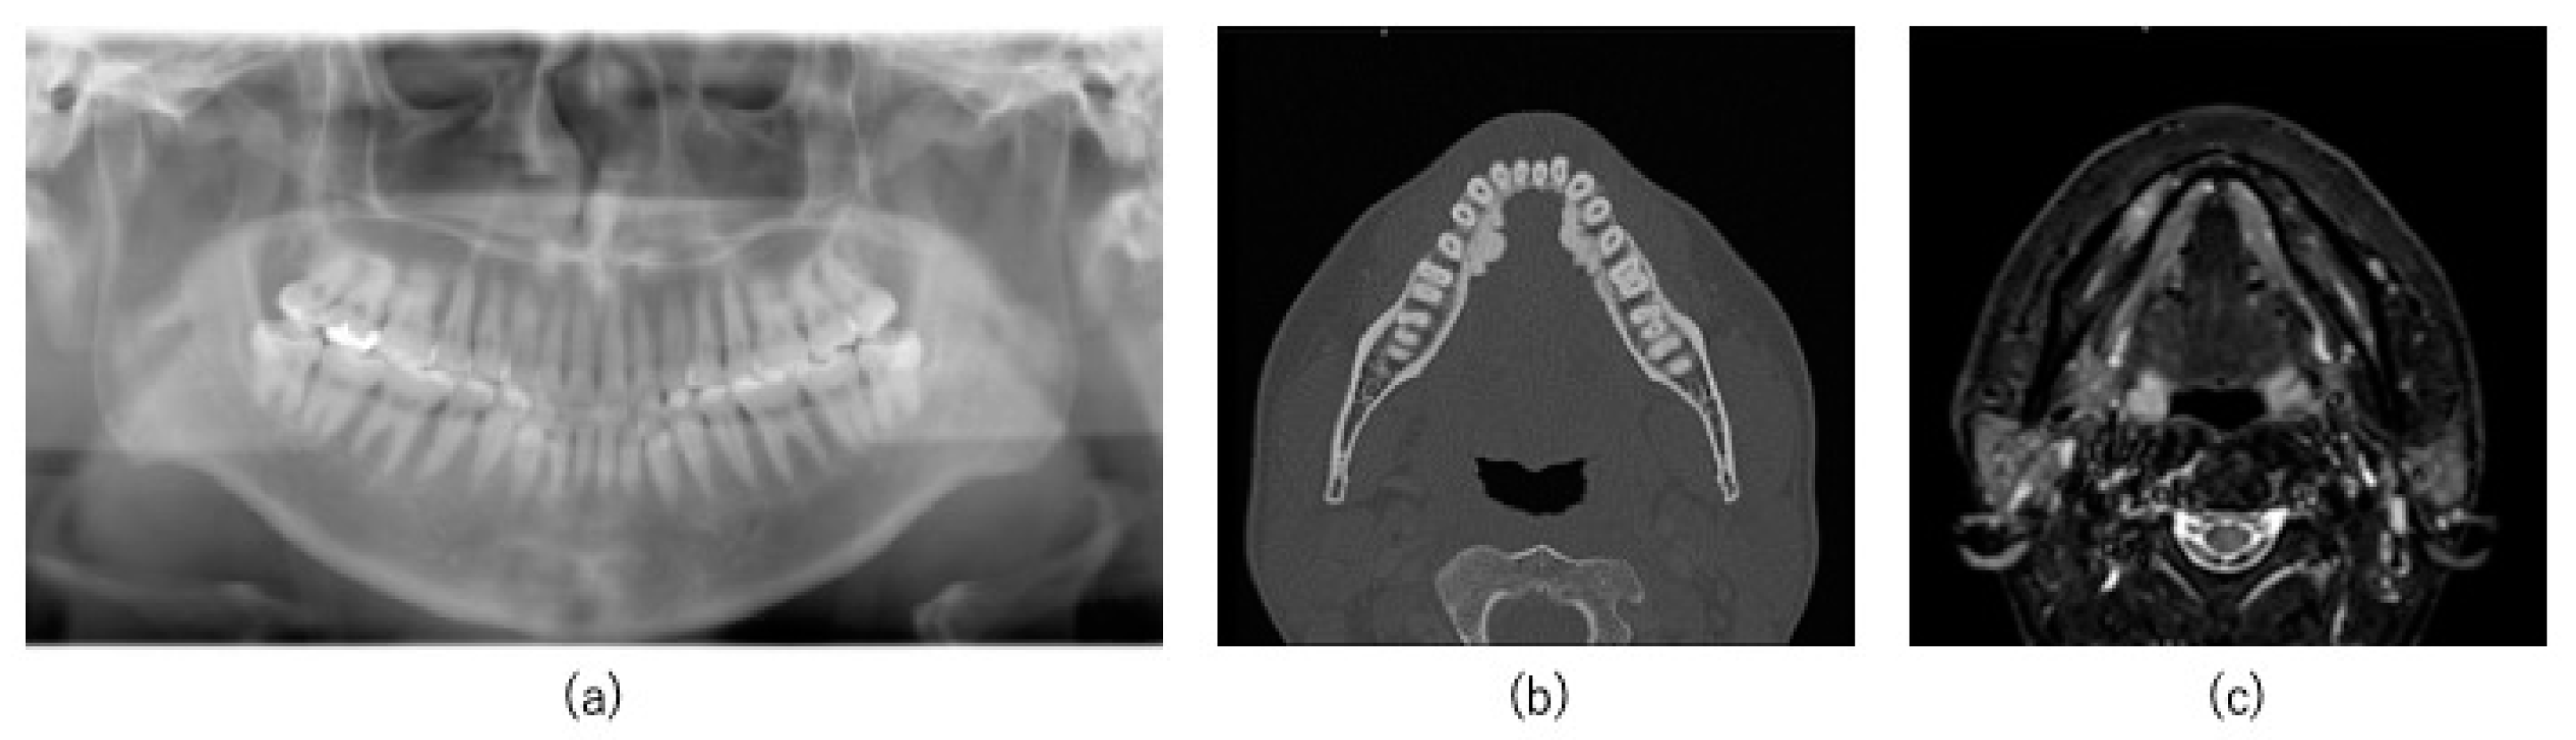

2.1. Case

2.2. Preoperative Preparation (CAD/CAM Osteotomy Guide, Virtual Surgery, and Fabrication of XR Application and Registration Marker)